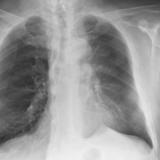

LUL Collapse Case 1 PA

Date: 02/19/2004

Views: 5531